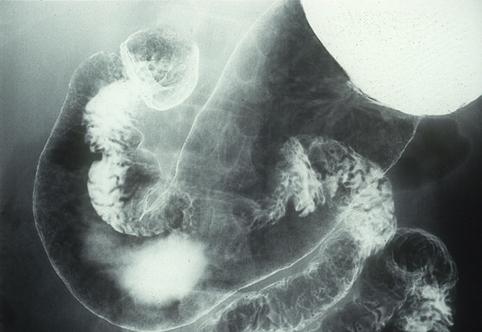

疾病(病理主体)的分类恶性上皮肿瘤/扁平上皮癌

检查方法X线